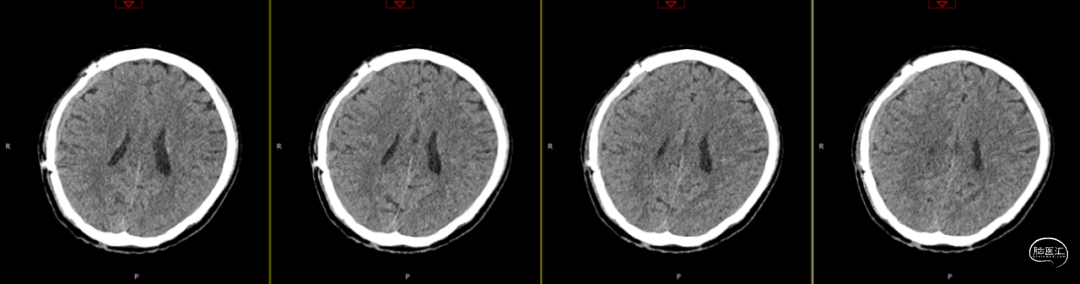

术后第1天颅脑CT复查(如上图)

查体:嗜睡-昏睡状态,精神差,刺激睁眼,简单应答,肢体活动简单从嘱。GCS13分。双侧瞳孔等大等圆,直径2.5mm,对光反射灵敏,伸舌欠合作。转头、耸肩欠合作,四肢肌力4级,肌张力正常,颈抵抗(+),双Babinski sign未引出。枕部可见约5*4cm皮下血肿,压痛,拒按。周身多发片状皮肤擦伤。颅脑CT:双侧额叶脑挫裂伤;右侧顶颞枕部硬膜外、硬膜下血肿;蛛网膜下腔出血;右侧颞骨骨折累及右侧人字缝、顶乳缝,右侧顶乳缝旁小骨片;头皮软组织损伤、局部皮下血肿;双肺挫伤可能。

因患者在病情观察期间意识状态变差,昏睡-浅昏迷状态,予以急症手术治疗,清除硬膜外血肿,鉴于术中脑组织压力不高,予以骨瓣回置,术后严格控制血糖水平,常规使用抗生素(头孢唑林钠)预防感染。